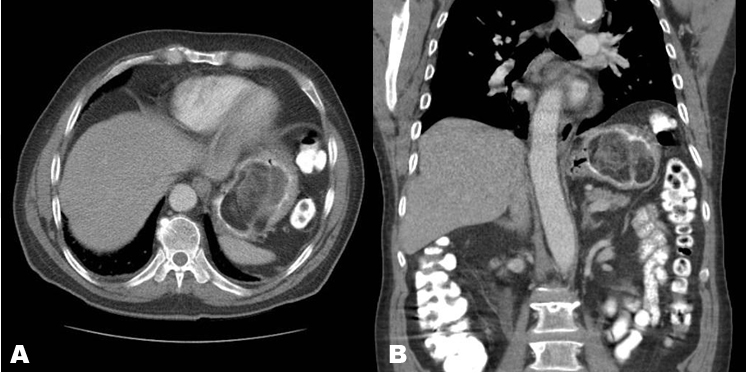

The patient is a 79-year-old male who presented to the emergency department for intermittent right upper quadrant abdominal pain with reported hematemesis and melena. His abdomen was soft and no masses were palpated. Serology was notable for a hemoglobin of 7.8 g/dl and hematocrit of 26.6%. The patient was admitted to the Internal Medicine service with the diagnosis of upper gastrointestinal bleed. Computed tomography (CT) examination with IV and PO contrast demonstrated a large mixed fat and soft tissue density intraluminal gastric mass (7.9x5.6x7.2 cm) originating from the greater curve consistent with a well-differentiated liposarcoma (Figure 1). No extraluminal extension was evident and no lymphadenopathy or metastases were present.

Figure 1: (A) Contrast-enhanced CT axial and (B) Coronal reformation images. Encapsulated intraluminal gastric mass arising from the greater curvature, 7.9x5.6x7.2 cm, with macroscopic fat and multiple thick internal septa, characteristic of a well-differentiated liposarcoma.